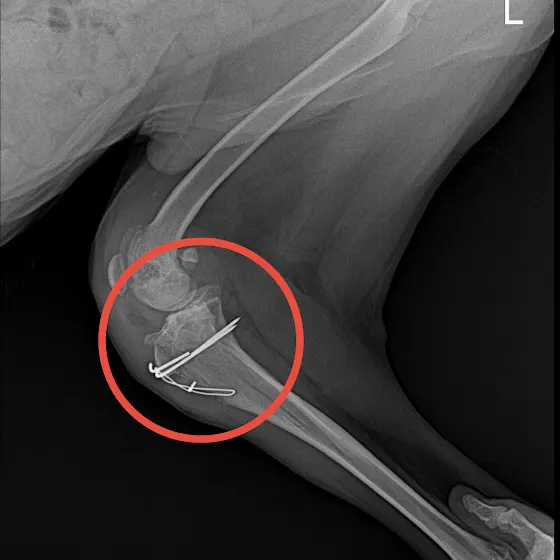

[3차수술] 현미

다리가 아픈친구라 쉼터생활이 힘들어서 저희집에서 지내며 치료후 미국으로 떠날 아이였지만 현미의 다리는 나날이 상태가 안좋아졌고 2차 병원 여러군데에서 진료를 보았습니다.

아직 어린 아기라 성장판이 있었기때문에 진통제를 먹으며 견뎌오다 드디어 기다리던 1차 수술을 했지만 실패로 돌아왔고 한달 후 2차 수술 역시 실패였습니다.

사고칠나이에 그냥 조용히 누워 자는 안쓰런 아이입니다. 우리 현미가 3차 수술을 마지막으로 더이상 수술대에 눕는일이 없길 바랍니다.